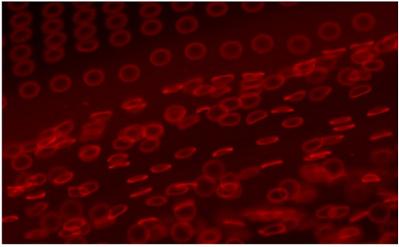

| Synthetic red blood cell mimics, shown releasing from an adhesive film into a drop of solvent. The particles were manufactured using PRINT (Particle Replication in Non-wetting Templates) technology, which allows scientists to produce micro- and nanoparticles with customized dimensions and properties. Image courtesy Timothy J. Merkel and Joseph M. DeSimone, University of North Carolina at Chapel Hill. |

University of North Carolina at Chapel Hill researchers used technology known as PRINT (Particle Replication in Non-wetting Templates) to produce very soft hydrogel particles that mimic the size, shape and flexibility of red blood cells, allowing the particles to circulate in the body for extended periods of time.

UNC researchers designed the hydrogel material for the study to make particles of varying stiffness. Then, using PRINT technology � a technique invented in DeSimone's lab to produce nanoparticles with control over size, shape and chemistry � they created molds, which were filled with the hydrogel solution and processed to produce thousands of red blood cell-like discs, each a mere 6 micrometers in diameter.